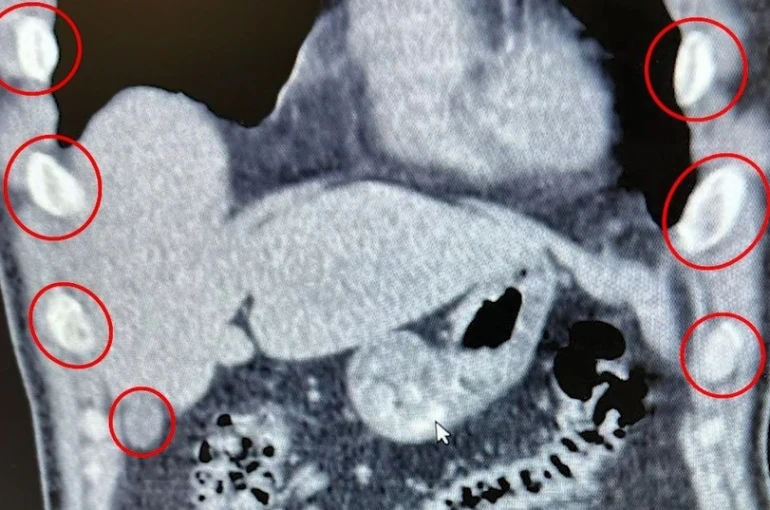

Bitlis İl Emniyet Müdürlüğü Narkotik Suçlarla Mücadele Şube Müdürlüğü ekipleri, uyuşturucu ile mücadele kapsamında önemli bir operasyona imza attı. Tatvan ilçesinde durdurulan bir otobüste yolcu olarak seyahat eden yabancı uyruklu 2 kişi gözaltına alındı. Şahısların yapılan tıbbi müdahalesinde, yuttukları 136 kapsül halinde toplam 1 kilo 48 gram metamfetamin ele geçirildi.